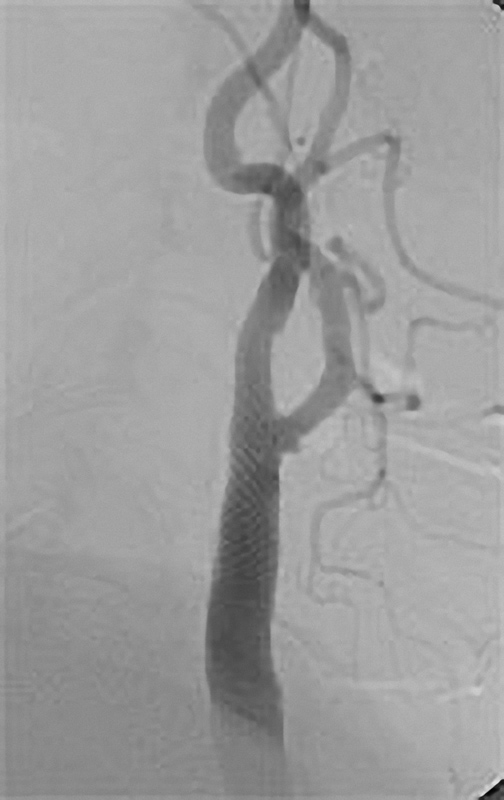

Einengung einer Beckenarterie

Die PTA (Perkutane Transluminale Angioplastie) im Beckenbereich ist ein minimalinvasives Verfahren zur Behandlung von verengten Beckenarterien. Dabei wird ein dünner Katheter mit einem Ballon über die Leiste in die verengte Arterie eingeführt. Der Ballon wird an der Engstelle entfaltet und dehnt die Arterie auf, um den Blutfluss zu verbessern. Oft wird zusätzlich ein Stent eingesetzt, um die Arterie dauerhaft offen zu halten. Die PTA wird meist in örtlicher Betäubung durchgeführt und ermöglicht eine schnelle Erholung. Sie ist eine bewährte Alternative zur offenen Operation bei Durchblutungsstörungen im Becken- und Beinbereich.